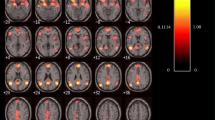

Moral sense is defined as a feeling of the rightness or wrongness of an action that knowingly causes harm to people other than the agent. The large amount of data collected over the past decade allows drawing some definite conclusions about the neurobiological foundations of moral reasoning as well as a systematic investigation of methodological variables during fMRI studies. Here, we verified the existence of converging and consistent evidence in the current literature by means of a meta-analysis of fMRI studies of moral reasoning, using activation likelihood estimation meta-analysis. We also tested for a possible neural segregation as function of the perspective used during moral reasoning i.e., first or third person perspectives. Results demonstrate the existence of a wide network of areas underpinning moral reasoning, including orbitofrontal cortex, insula, amygdala, anterior cingulate cortex as well as precuneus and posterior cingulate cortex. Within this network we found a neural segregation as a function of the personal perspective, with 1PP eliciting higher activation in the bilateral insula and superior temporal gyrus as well as in the anterior cingulate cortex, lingual and fusiform gyri, middle temporal gyrus and precentral gyrus in the left hemisphere, and 3PP eliciting higher activation in the bilateral amygdala, the posterior cingulate cortex, insula and supramarginal gyrus in the left hemisphere as well as the medial and ventromedial prefrontal cortex in the right hemisphere. These results shed some more light on the contribution of these areas to moral reasoning, strongly supporting a functional specialization as a function of the perspective used during moral reasoning.